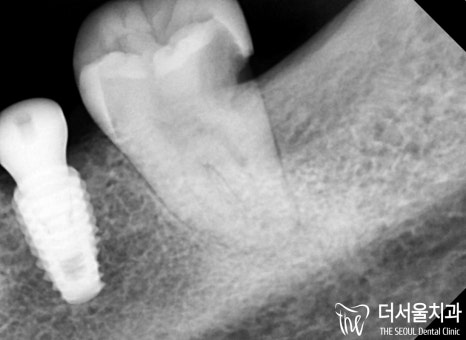

더서울에서 확인을 해보니

문제는 한곳이 아니었습니다.

검게 물들어 있는 것이 보입니다.

아마 치관을 넘어 치근에도

영향을 끼치지 않았을까 판단이 되네요.

뭐 위생관리가 잘 된다면 다행이지만,

맨 뒤쪽에 위치해있기 때문에

스스로 청결한 관리를 하는 게 쉽지 않죠.